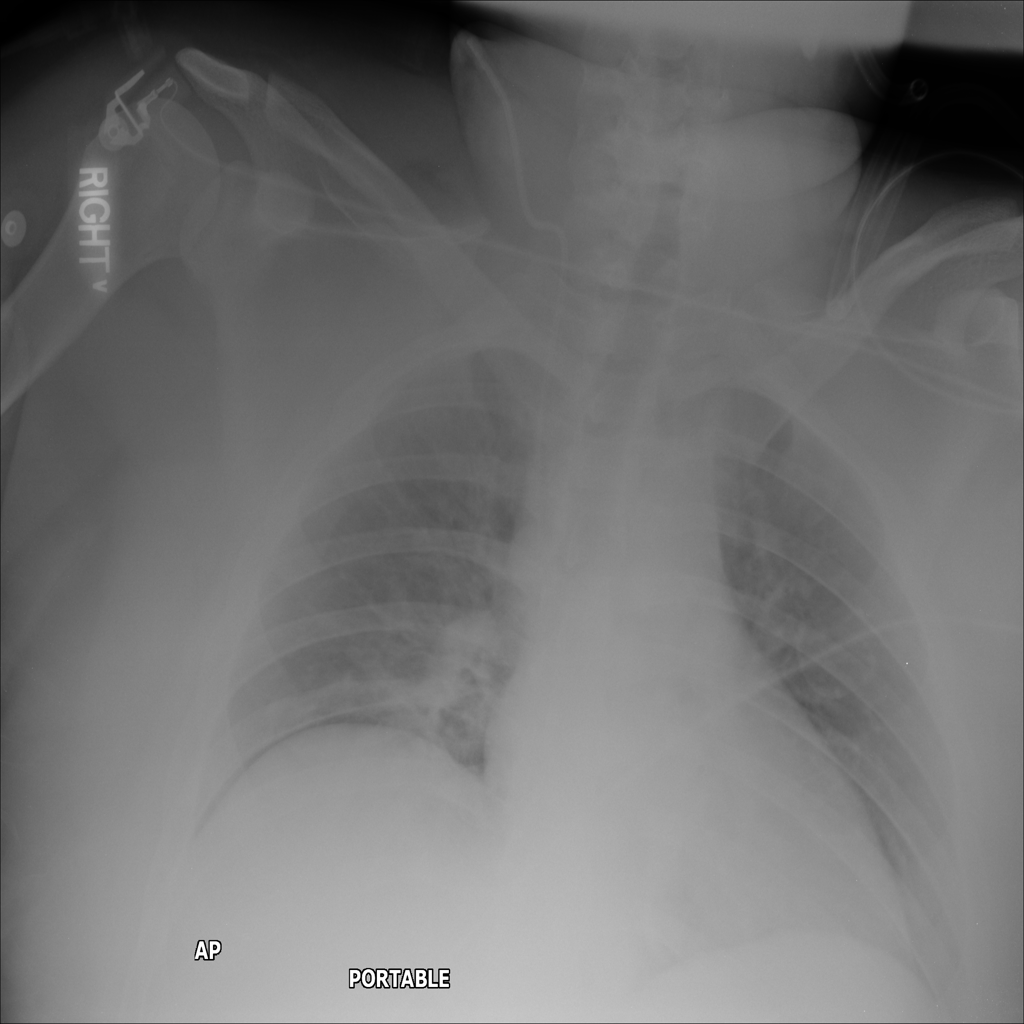

PAT-C1A7 · IMG-055Consolidation

PAT-C1A7 · IMG-055

AP